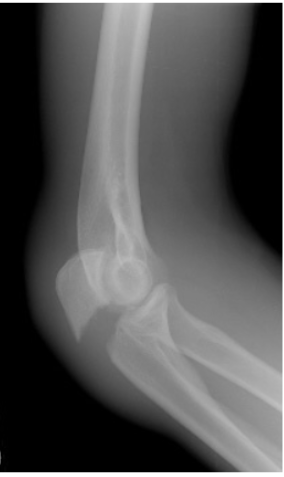

Mecanismo de lesion de esta fractura

Fractura de la parte LATERAL del radio —> rotacion externa con carga axial al codo con fuerza combinada de valgo

Clasificacion de Mason de esta fractura

Tipo 1: fisura o fractura marginal con <2mm de desplazamiento

Tratamiento de fractura de mason tipo 1

Cabestrillo